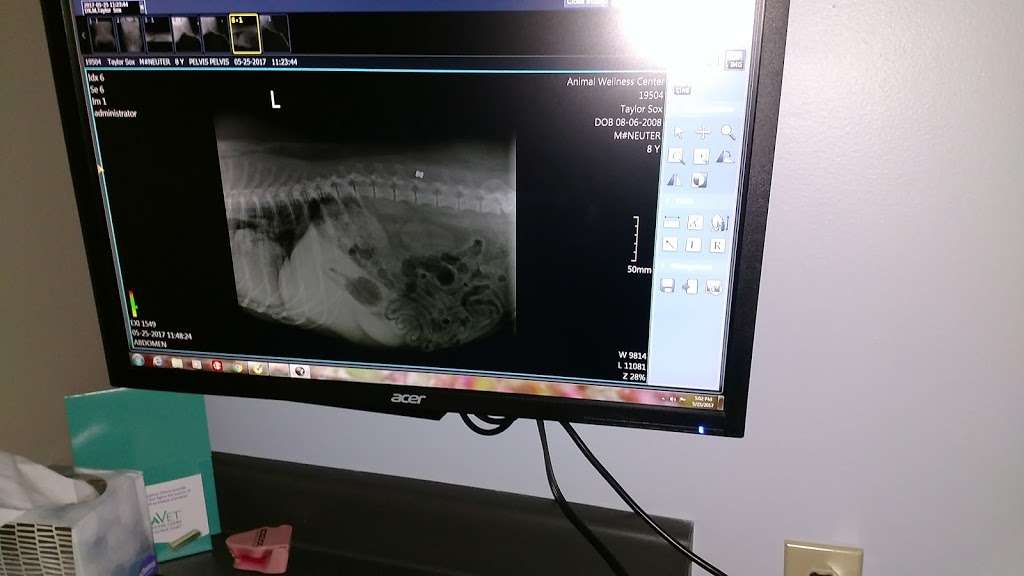

Animal Wellness Center of Pontiac is a full-service veterinary medical and surgical facility located in Pontiac, Illinois. Animal Wellness Center of Pontiac offers many advanced veterinary services and outpatient surgical procedures and radiography and other surgical procedures requiring hospitalization.